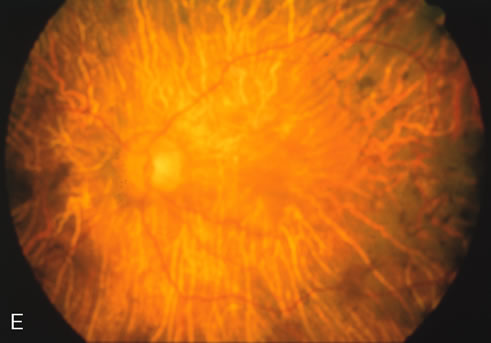

Fluorescein angiography highlights observable fundus findings. In patients with a golden reflex the FA is normal (Fig. 2E, F) or shows a mild transmission hyperfluorescence.7